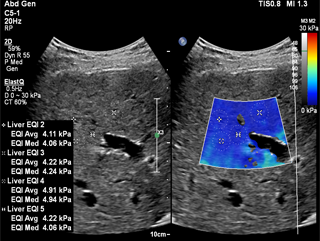

L’imagerie échographique ElastQ est l’évaluation quantitative avec codage couleur de la dureté des tissus, en temps réel, sur une large région d’intérêt (ROI). Les cliniciens peuvent facilement évaluer la rigidité hépatique en temps réel et prendre des mesures quantitatives avec plusieurs points d’échantillonnage. L’imagerie échographique ElastQ offre également la possibilité de réaliser des mesures rétrospectives sur des images stockées. L’affichage de la cartographie de fiabilité unique fait appel à l’analyse intelligente des structures, qui indique à l’utilisateur les zones de tissu soumis à une propagation appropriée des ondes de cisaillement et renforce l’assurance de ses mesures.